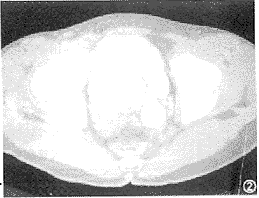

腹部平片不能显示囊肿,如囊肿并发结石,偶尔可根据结石存在的部位,推测本病的可能。在排泄性尿路造影上,造影剂聚集在囊样扩张的输尿管和膀胱内,显示为圆形或卵圆形的致密影,由于突入段输尿管壁本身的厚度和覆盖在其上面的膀胱粘膜的投影,产生包绕囊肿周围的透光晕,从而构成“蛇头”样表现[3] (图1)。

图1 排泄性尿路造影显示左侧输尿管下端囊状扩张向膀胱内突出,呈“蛇头”样 图2 同一病例,CT增强扫描,左侧输尿管下端囊状扩张并疝入膀胱内,其壁呈环形低密度影